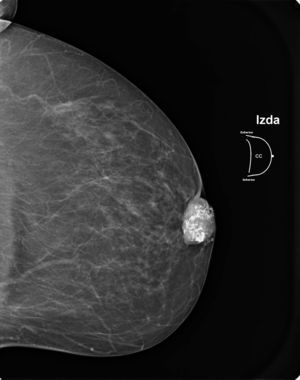

Presentamos el caso de una mujer de 86 años, con antecedentes personales de bronquitis crónica, tuberculosis pulmonar, hipertensión arterial, fibrilación auricular en tratamiento con anticoagulantes orales y colecistectomía, que acudió a consulta por presentar tumoración retroareolar en la mama izquierda. A la exploración presentaba una masa de unos 4–5cm, de consistencia pétrea y que producía retracción del pezón. No se palparon adenopatías axilares. En la mamografía se apreció, en el área retroareolar de la mama izquierda, una imagen nodular de 3×2,5×4cm de diámetro con densa calcificación en su interior (fig. 1), asociada a engrosamiento cutáneo. La lesión estaba bien delimitada y no se apreciaban áreas con espiculación. Los hallazgos correspondían a la categoría BI-RADS IV. Se realizó biopsia con tru-cut que permitió llegar al diagnóstico de carcinoma metaplásico productor de matriz. El estudio de extensión fue negativo.